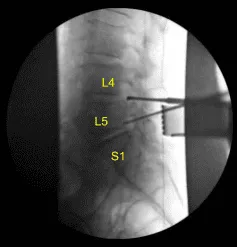

Hicimos una radiografía final que confirmó la descompresión de los forámenes con un Woodson y un Penfield #4 en los forames L4-5 y L5-S1 del lado izquierdo. La herida fue irrigada abundantemente. Se confirmó hemostasis.